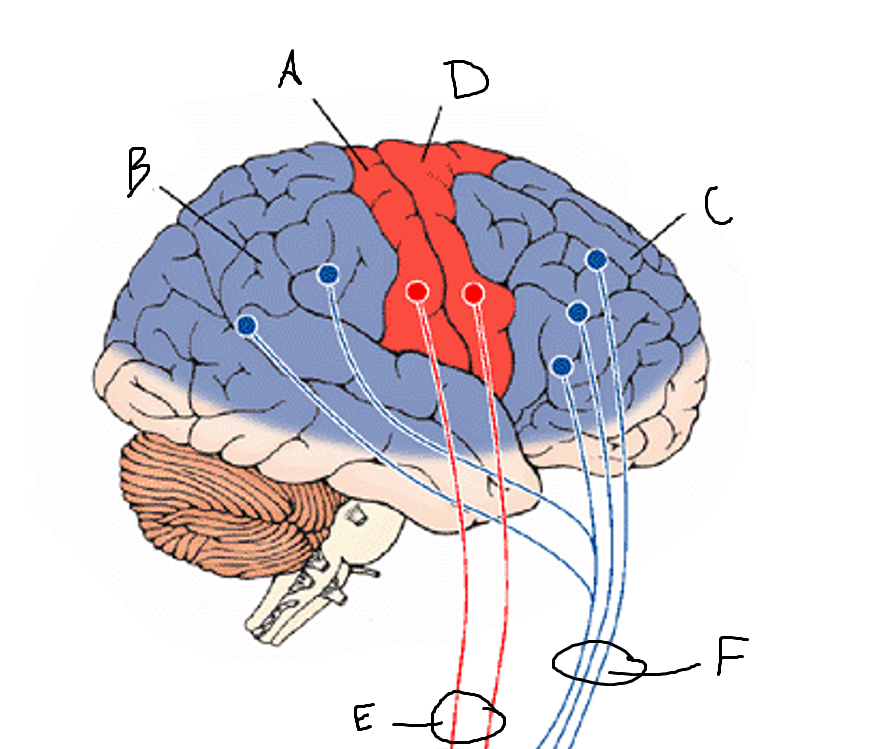

basal ganglia

A

somatosensory cortex

B

parietal association cortex

C

frontal and prefrontal cortices

D

primary motor cortex

E (where are the projections?)

putamen

F (where are the projections?)

caudate